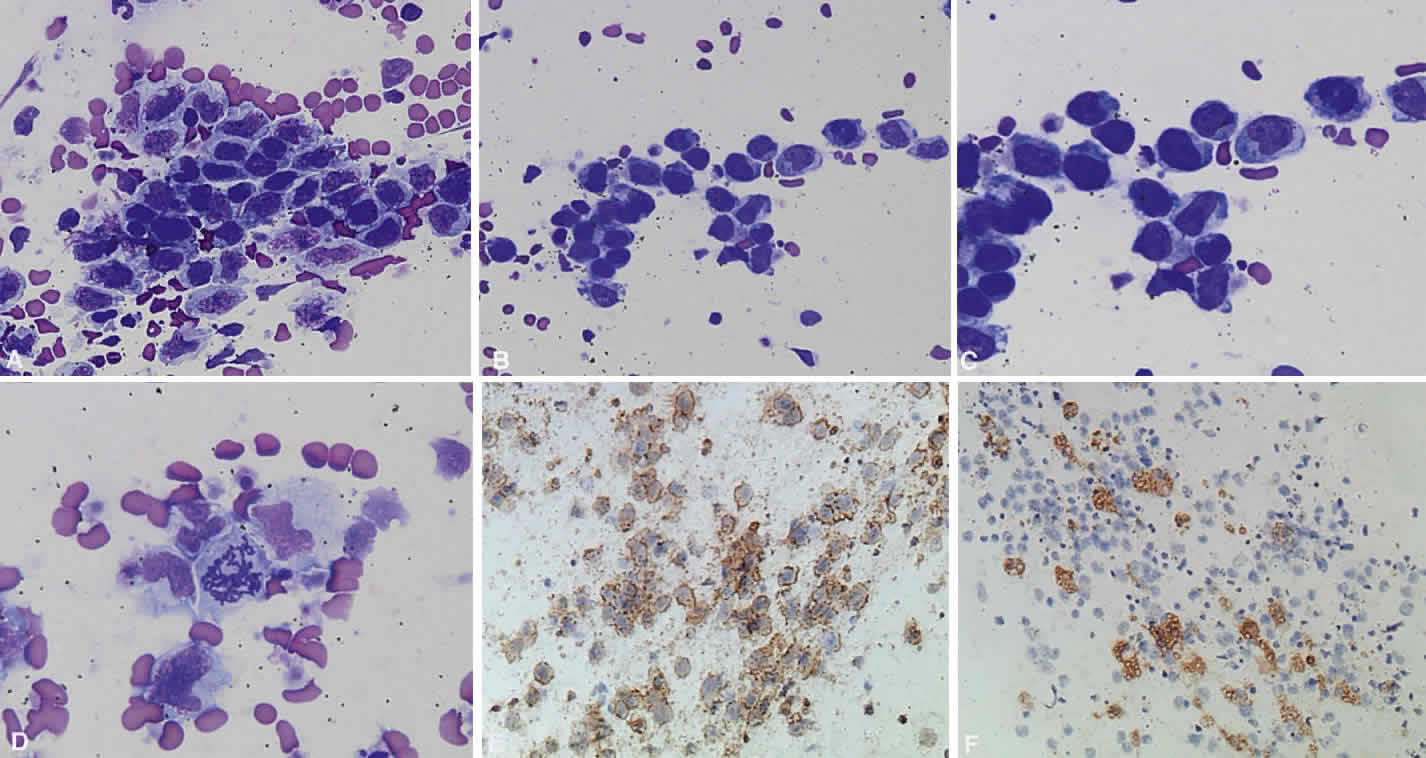

Systemic non-Hodgkin's lymphomas usually present with painless lymph node enlargement in one or more nodes. Adults usually are in their fifth or sixth decade, and presentation in childhood is extremely rare. The fever, night sweats, and weight loss characteristic of Hodgkin's disease generally are absent. Splenomegaly may develop in 20% of patients. Patients usually have normal blood counts, although they may develop lymphocytosis, especially with well-differentiated lymphocytic lymphomas, or pancytopenia with anemia, hemorrhage, petechiae, ecchymosis, and infection—the pancytopenia occurring in one third of patients as a result of bone marrow involvement or chemotherapy and radiation. Patients with B-cell lymphomas tend to develop difficulty with bacterial infection, whereas those with T-cell lymphoma may develop difficulty with delayed-type hypersensitivity and viral infections. Leukemic conversion is rare in adults, although it occurs in 25% of children. In children, an acute leukemic phase may be the initial presentation. Furthermore, children are more likely to develop extranodal and aggressive disease, although they may respond well to therapy.50 In a series of 1269 patients, of whom only 3 (0.42%) presented initially with proptosis, one third of patients presented with extranodal disease and a few with bone marrow invasion.51 There was a 1.3% incidence rate of orbital disease secondary to systemic lymphoma.